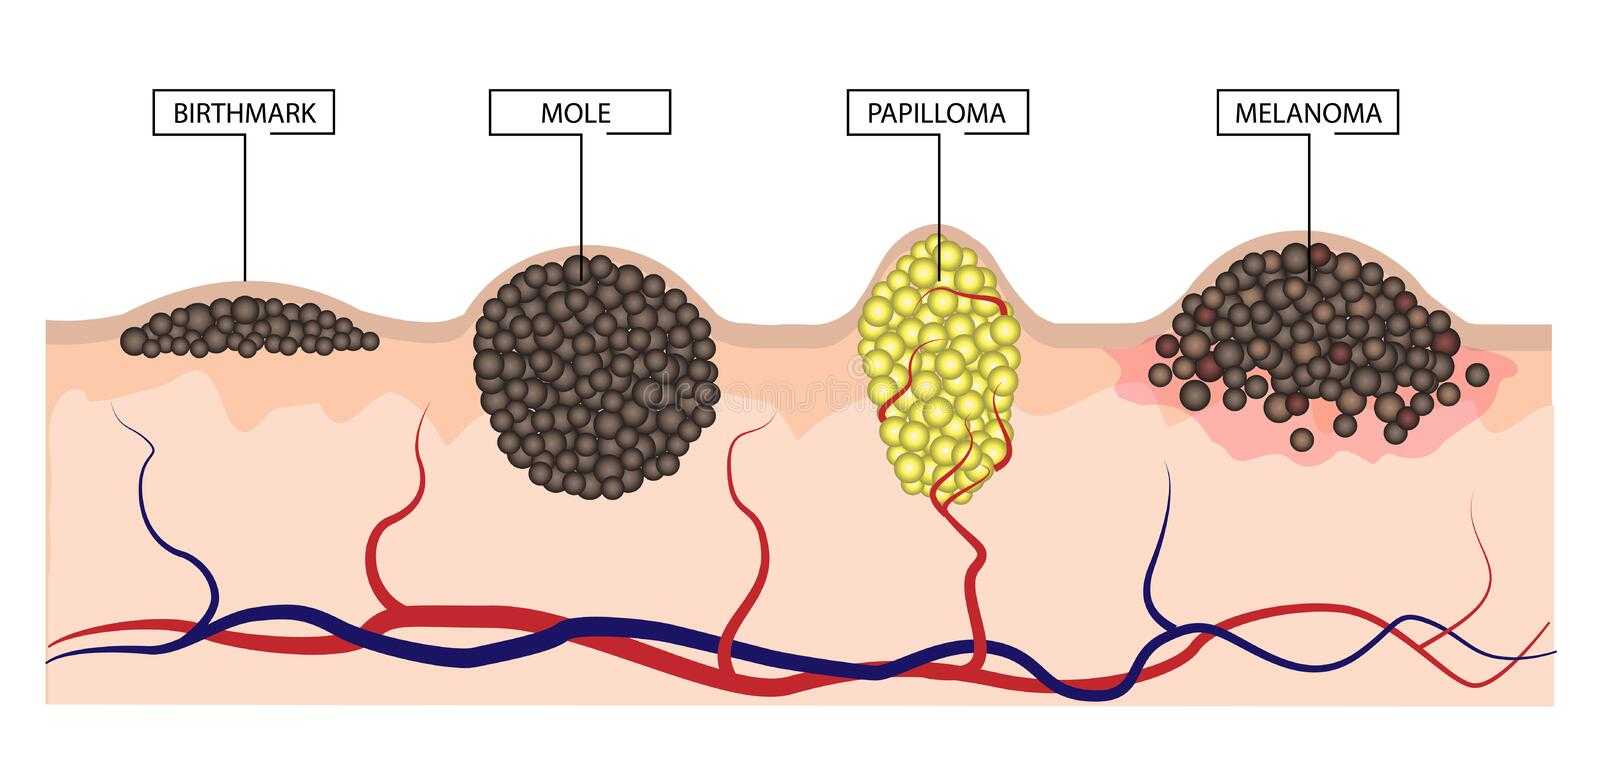

Кондиломы - это одно из самых распространенных заболеваний, передающихся половым путем. Они вызваны вирусом папилломы человека (ВПЧ) и могут появляться на внешних половых органах, анусе, ротовой полости и других областях тела.

Симптомы кондилом могут варьироваться, и визуальное представление этого заболевания может быть различным. Некоторые кондиломы выглядят как небольшие бугорки или бородавки, в то время как другие могут иметь форму плоских пятен или цветных наростов.